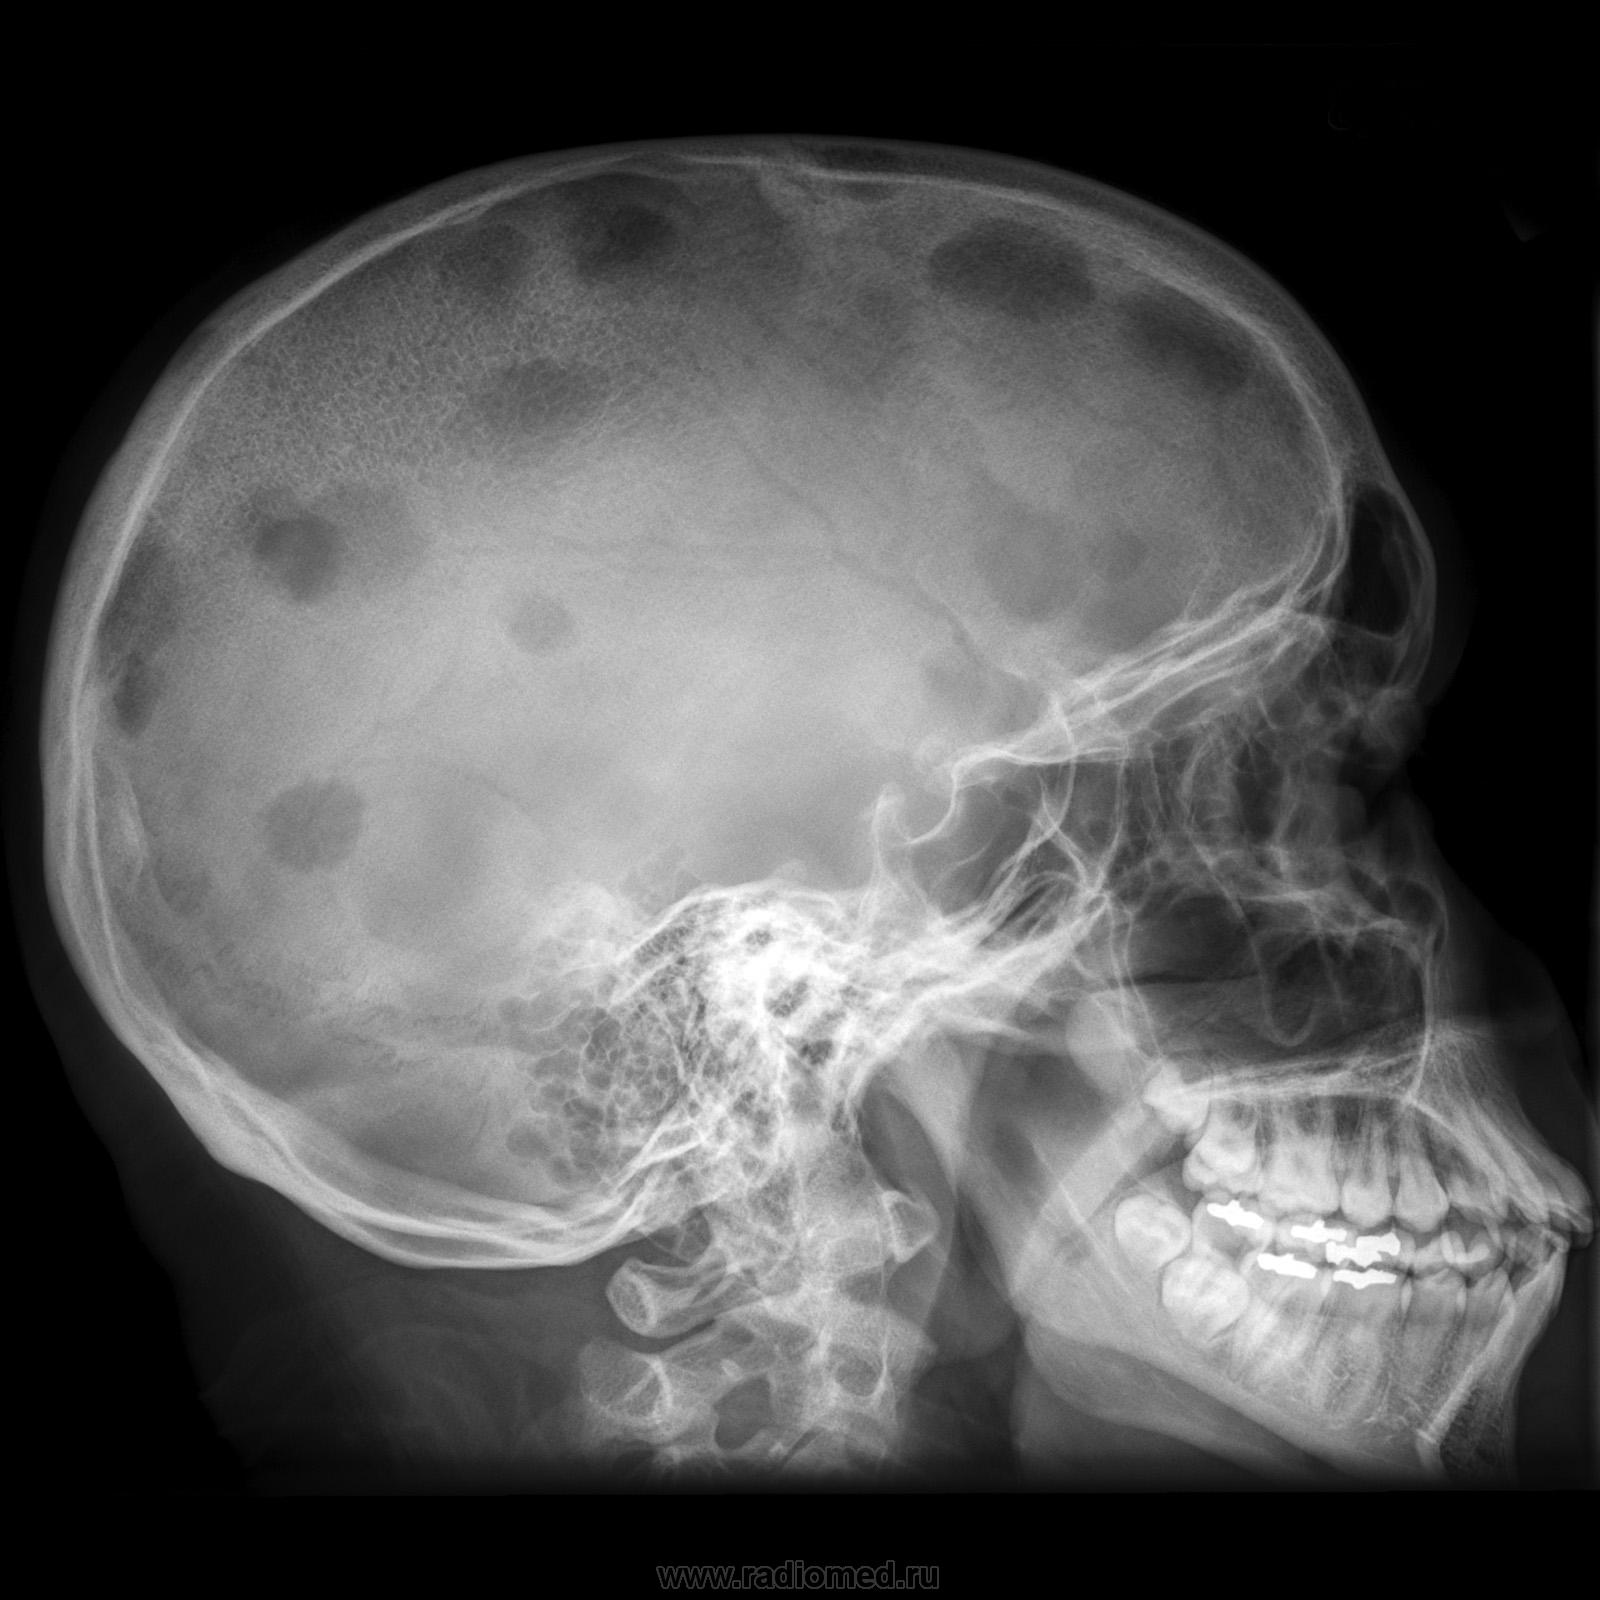

Повреждения свода черепа при саркоидозе редки, в литературе сообщалось о менее 30 случаях. Частота такого состояния может быть недооценена, поскольку симптомы как правило отсутствуют или минимальны, например головная боль или местная опухоль. Костные лакуны бывают различными по размеру и локализации. Рентгенограмма обычно демонстрирует остеолиз с уменьшением толщины черепа, без уплотнений вблизи повреждений. Сообщалось о случаях частичного или полного регресса повреждений, спонтанного или после лечения. Поражение других черепных костей, то есть пазух, каменистой части височной кости, глазниц, нижней челюсти и носовой кости, часто обнаруживается при использовании КТ"

Череп, конечно, полный эксклюзив.

"Саркоидоз черепа". Правильно пословица глаголет, что век живи, век учись...